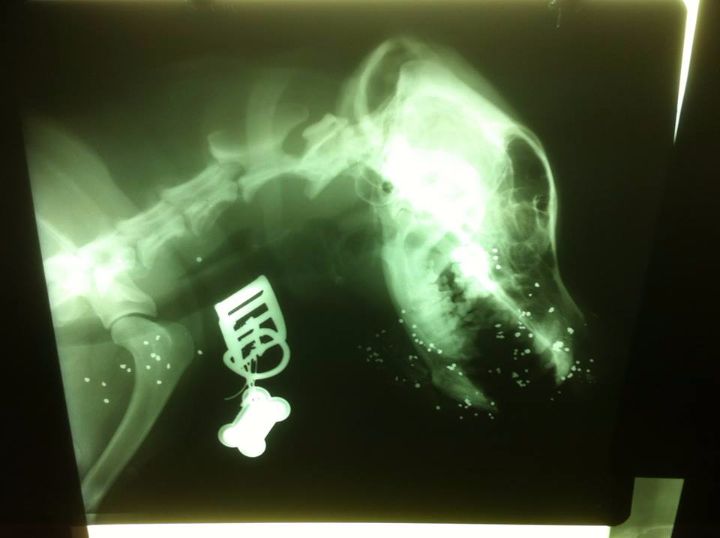

Η ακτινογραφία έδειξε τα σκάγια διάσπαρτα στο κεφάλι του ζώου.

Το σκυλί επέστρεψε το μεσημέρι στις 15:00 στο σπίτι του αιμόφυρτο με μια τρύπα στο ρουθούνι του με διάμετρο μεγαλύτερη από τρία εκατοστά . Το τραύμα από τον πυροβολισμό ήταν διαμπερές καθώς τα σκάγια βγαίνοντας θρυμάτισαν την κάτω γνάθο του σκύλου.

Ο κ. Παυλιδάκης μετέφερε το σκυλί του για να το σώσει στο κτηνιατρείο της Ελένης Μαρουλάκη και εκεί οι ακτινογραφίες έδειξαν τι έχει συμβεί. Το ζώο πυροβολήθηκε εξ επαφής αλλά προφανώς κατά την εκπυρσοκρότηση, του δράστη του έφυγε η καραμπίνα προς τα κάτω, γι? αυτό και διέλυσε τελείως τοκάτω αριστερό μέρος της γνάθου.